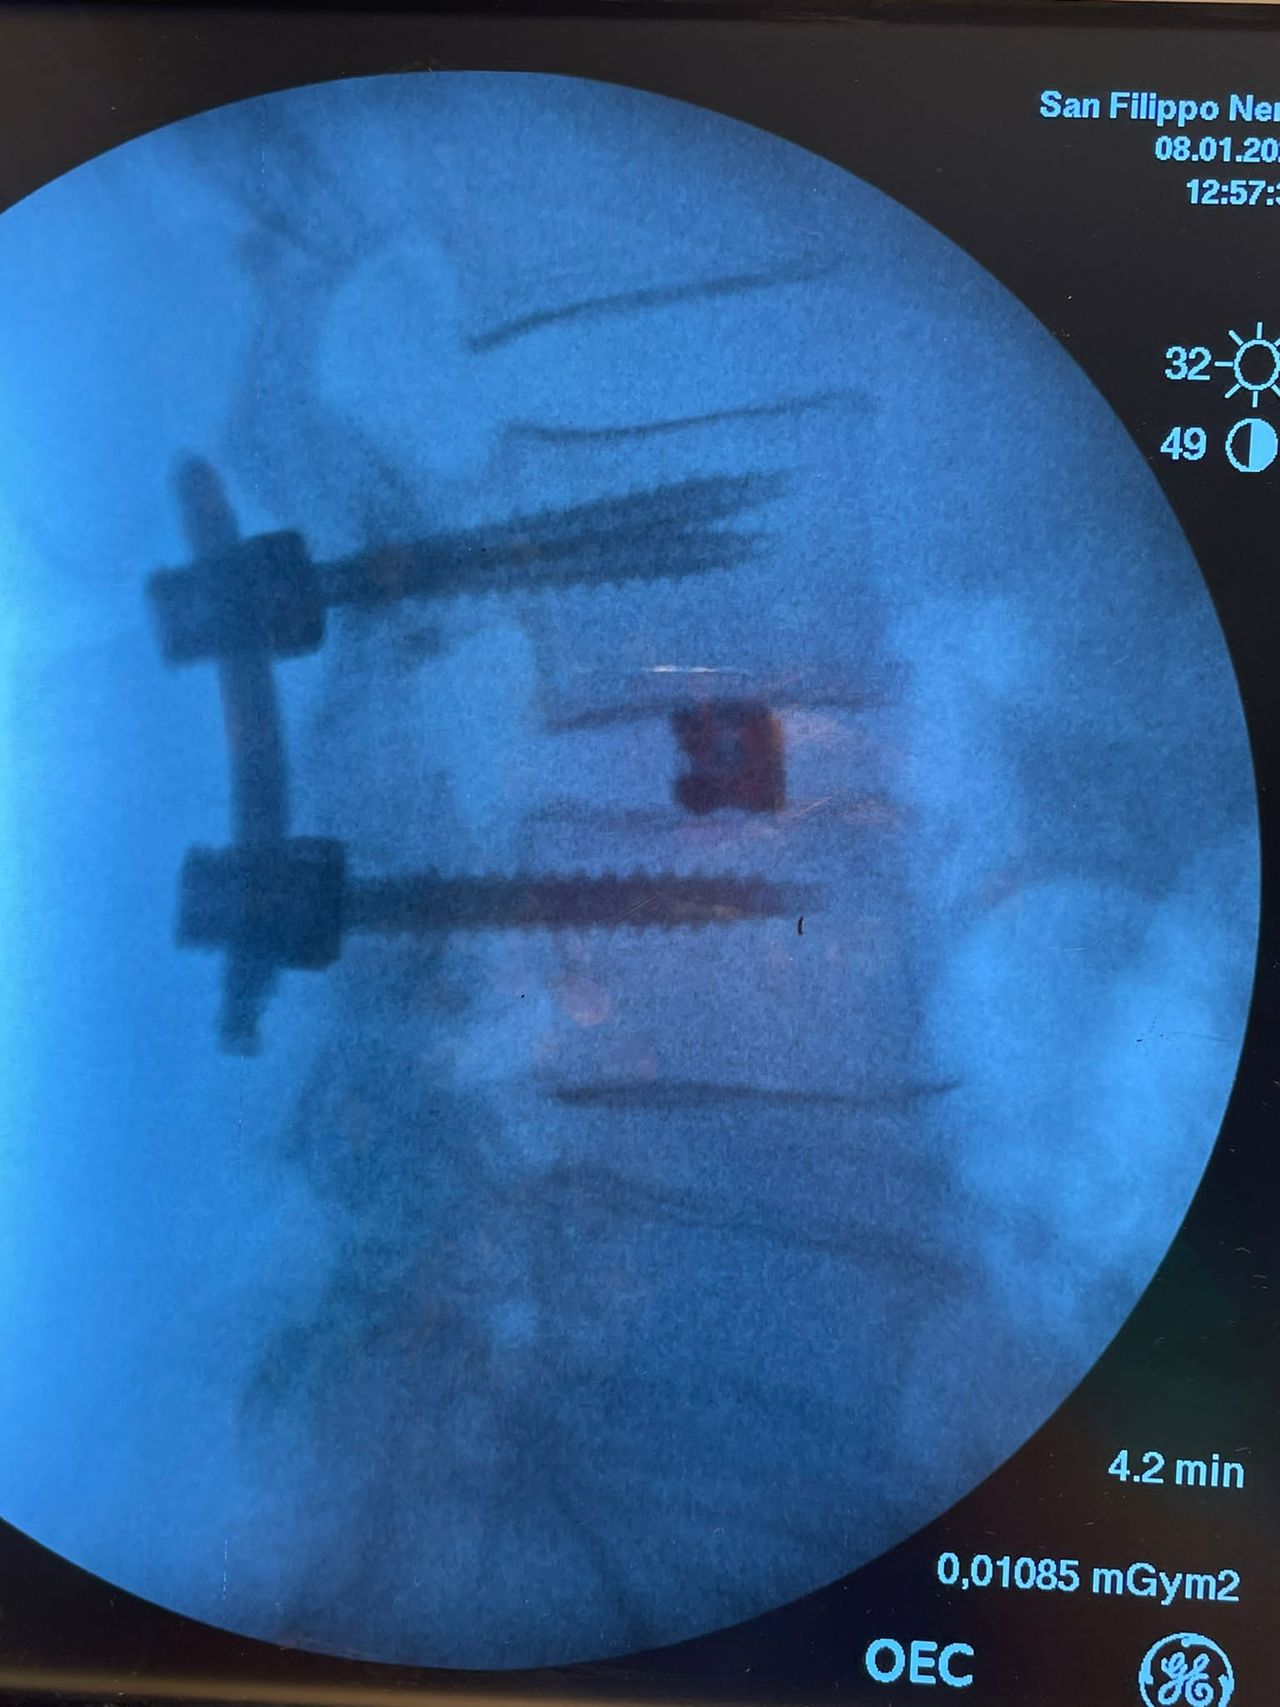

Dirigente Medico presso l’UOC Neurochirurgia dell’Ospedale San Filippo Neri di Roma.

- Chirurgia Mininvasiva percutanea vertebrale - stabilizzazioni e artrodesi intersomatiche (per fratture vertebrali, spondilolistesi, instabilità vertebrali, discopatie)

- RX scopia intraoperatoria